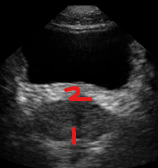

Identify this image.

Prostatic apex

Prostatic base